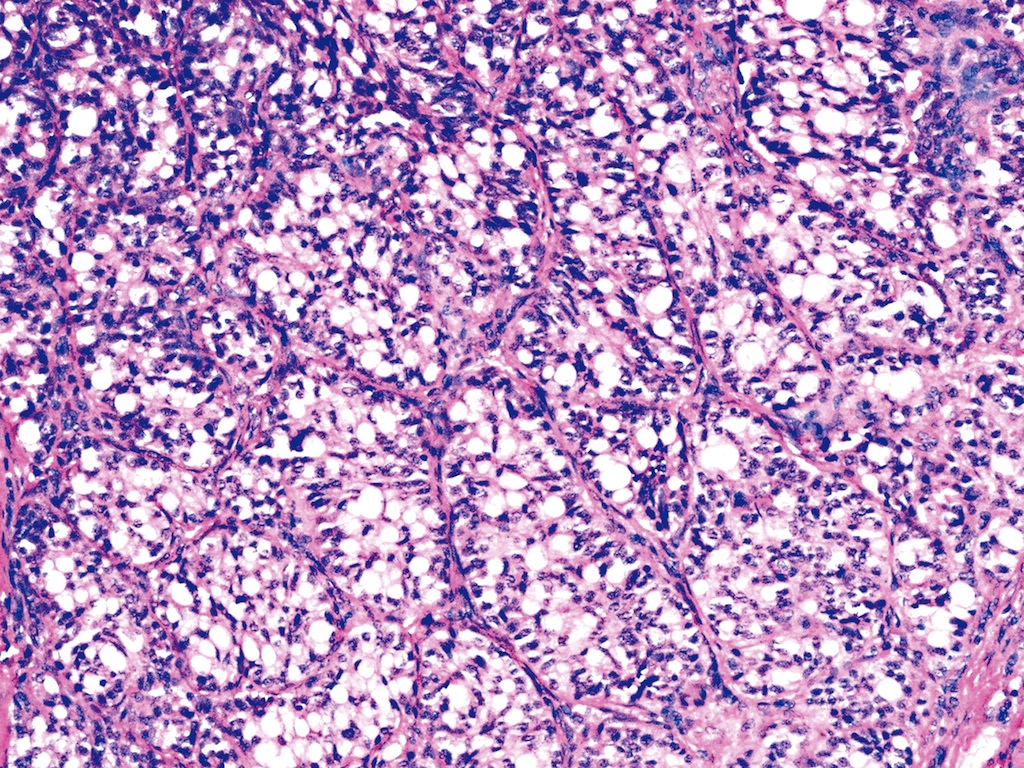

Microscopic (histologic) description

- Wide variety of morphology, can mimic any other thyroid malignancy

- Round, plasmacytoid, polygonal or spindle cells in nests, cords or follicles; often mixtures of these cells

- Round nuclei with finely stippled to coarsely clumped chromatin and indistinct nucleoli, occasional nuclear pseudoinclusion

- Eosinophilic to amphophilic granular cytoplasm due to secretory granules

- Generally low mitotic figures

- Stroma has amyloid deposits from calcitonin, prominent vascularity with glomeruloid configuration or long cords of vessels (Am J Surg Pathol 1995;19:642), coarse calcifications, occasional psammoma-like bodies

Variants (important for differential diagnosis, most are of no prognostic importance):

- Clear cell variant (Hum Pathol 1985;16:844)

Microscopic (histologic) images

Contributed by Shuanzeng Wei, M.D., Ph.D., Joseph Christopher Castillo, M.D. and Mark R. Wick, M.D.

AFIP images

Images hosted on other servers: